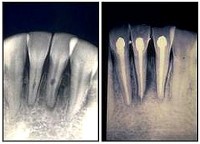

Imágenes de un tratamiento endodóntico y su posterior restauración con material estético Deja un comentarioYou must be logged in to post a comment.